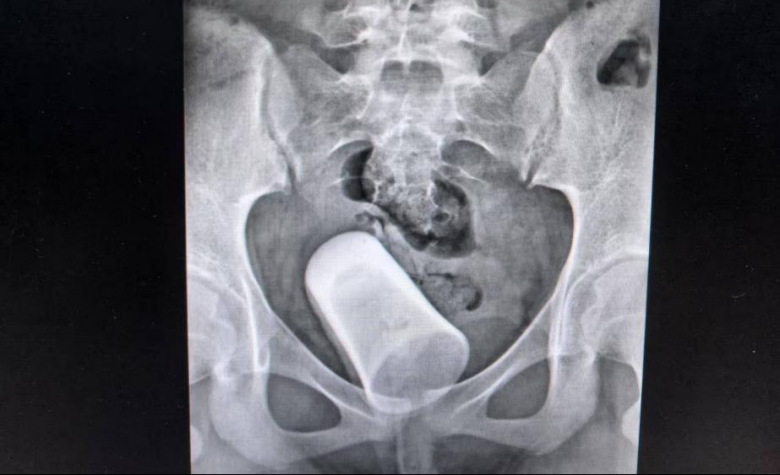

据了解,患者小Y不能憋尿伴夜间遗尿有段时间了,但是家属未予重视。后因发现有异物才前往就诊。当天接诊的医生在接诊患者进行查体,并行盆腔平片检查提示:盆腔内见杯状致密影,大小约85mm*45mm。该院迅速组织多学科疑难病例进行讨论,在一系列相关检查后,行阴道内异物取出术。整个过程顺利,但是阴道里的异物竟然是一支玻璃杯,着实让大家吃惊。